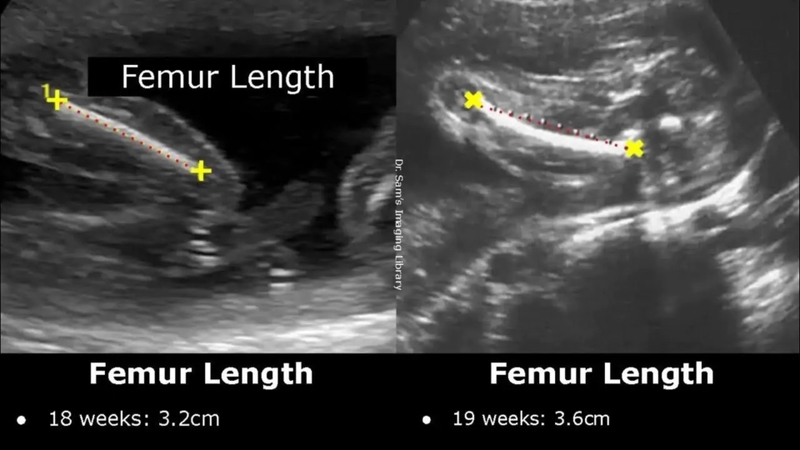

• FL (Femur length): Chiều dài xương đùi thai nhi.

Bảng chiều dài xương đùi thai nhi tiêu chuẩn theo tuần

Độ dài xương đùi thai nhi là một chỉ số quan trọng, gắn liền với sự lớn lên của thai nhi. Vì vậy, chỉ số chiều dài xương đùi thai nhi tiêu chuẩn cũng sẽ thay đổi theo từng tuần tuổi của thai.

Các bà mẹ có thể tham khảo bảng dưới đây để theo dõi sự lớn lên của thai và từ đó điều chỉnh lại chế độ ăn, thói quen hàng ngày để cải thiện chỉ số. Bên cạnh đó, các bố mẹ chỉ nên siêu âm, khám thai tại các mốc định kỳ hoặc theo sự chỉ dẫn của bác sĩ. Tránh việc siêu âm quá thường xuyên ảnh hưởng đến sự phát triển của thai.